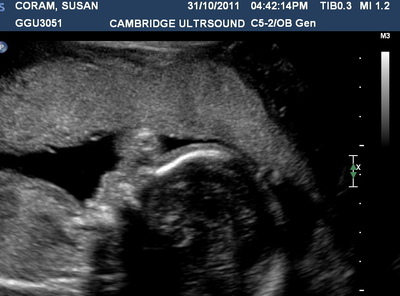

After the initial shock (which lasted only a few minutes) excitement settled in. It was also with much excitement we discovered at our 20 week scan that we were having a boy.